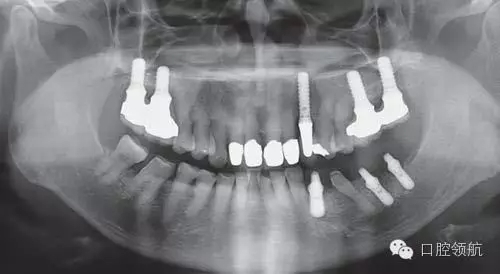

來自于外院的下頜左側(cè)種植病例,術(shù)前X線片診斷嵴頂距下頜神經(jīng)管骨量充分,一次手術(shù)方法植入種植體,第2天頦孔區(qū)有輕微感覺異常,手術(shù)醫(yī)生了解后只是讓隨診觀察,但4個(gè)月后癥狀沒有改善,來我院要求進(jìn)一步檢查。

利用曲面斷層及CBCT檢查埋入部位情況,雖未出現(xiàn)與主訴相關(guān)的神經(jīng)損傷,但無意中卻發(fā)現(xiàn)了種植體的舌側(cè)穿孔(圖1、圖2)。

圖1 術(shù)后的曲面斷層影像。

雖不能確定是裂鉆備洞還是植入種植體所造成的穿孔,但從4個(gè)月的病情的發(fā)展看,考慮可能是術(shù)中的舌下動(dòng)脈損傷導(dǎo)致口底軟組織內(nèi)出血而造成的感覺異常。采用常規(guī)藥物及物理療法開始進(jìn)行治療。